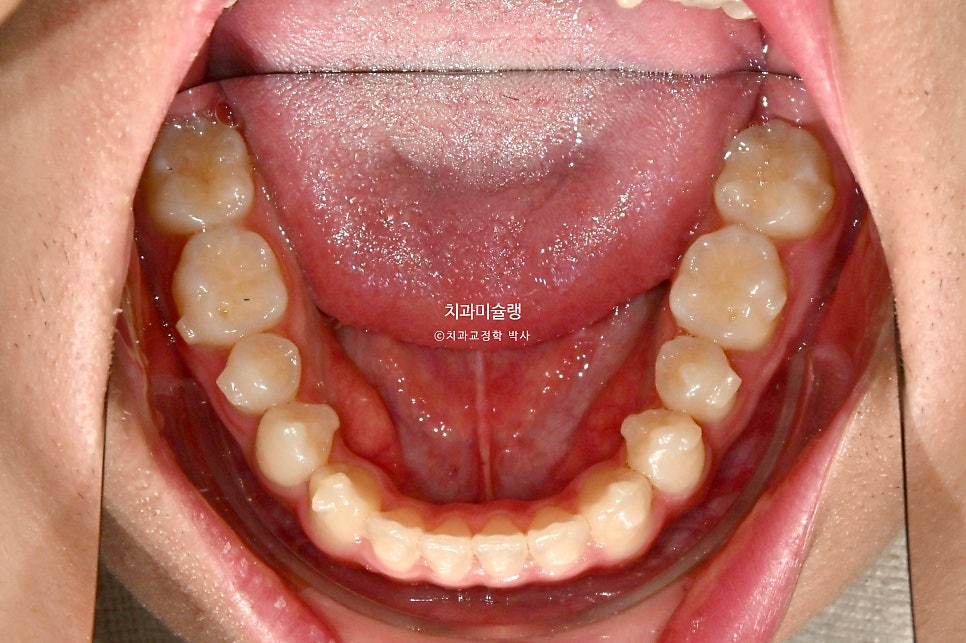

초진 시 구강 상태

제작년 유학중 여름방학을 맞이해 찾아온 만 15세 친구 입니다.

어릴때부터 소아치과에서 주기적으로 체크를 받아오며 교정이 필요없다는 이야기를 들었으나

최근 유학중 1-2년 사이 아래턱이 자란것같아 교정이 필요해보여 내원했습니다.

위 앞니가 벌어져있고 일부 개방교합이 보입니다.

어금니 교합관계는 3급이며 윗니가 아랫니를 덮지 못하는 절단교합 입니다.

옆에서 보면 이런 교합상태.

아래턱이 위턱에비해 앞으로 더 자라나온 골격성 3급 부정교합, 즉 주걱턱 입니다.

양악 수술 없이도 교합은 맞춰줄수 있는 정도라 교정만 하기로 했습니다.

만 15세라 성장이 아직 남아있다면 성장 종료시점까지 아래턱이 더 자라나올 수 있으므로 치료를 연기해야 하지만, 손 엑스레이 성장판 사진을 보니 성장이 완료되어 교정치료를 시작할 수 있는상태입니다.